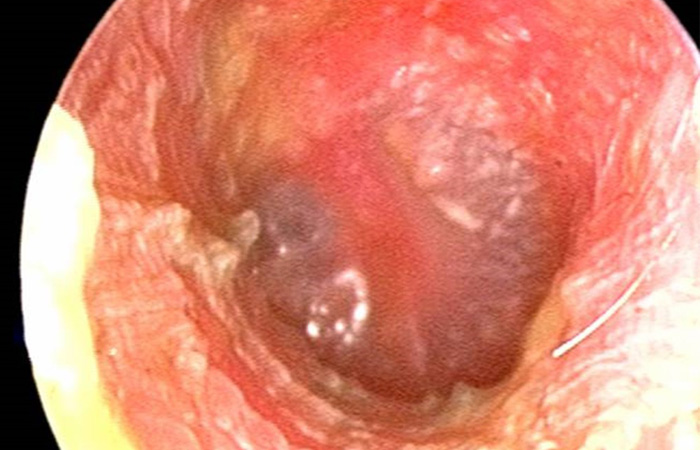

On examination, the ear canal is red and may be swollen.

Figure 1 shows an otoscopic picture of a normal ear canal; Figure 2 shows the ear canal as red and swollen, with the presence of debris and ear discharge. There may also be swelling and, in severe cases, there may be occlusion of the ear canal.

Above: Figure 2: Otitis externa showing inflamed ear canal and debris. With thanks to Department of Paediatrics, University of Wisconsin. pediatrics.wisc.edu/education/acute-otitis-media/exercises/images